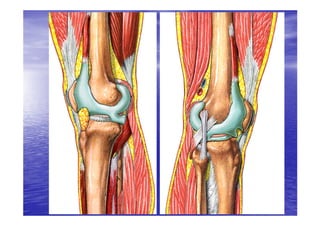

MOYENS D’UNION

LIGAMENTS ACTIFS

LIGAMENTS ACTIFS(1)

• ce sont les muscles qui

contribuent à la stabilité

articulaire par leurs

terminaisons tendineuses :

•   En avant : le tendon du

quadriceps qui se continue

par le ligament rotulien. Ainsi

se trouve formé le système

extenseur du genou

composé : du muscle

quadriceps, la patella et les

tendons rotulien et du

quadriceps

LIGAMENTS ACTIFS(2)

• En arrière : le

demi

membraneux,

membraneux, le

biceps crural et

le poplité.

LIGAMENTS ACTIFS (3)

• Médialement : les

muscles de la « patte

d’oie » (couturier ou

sartorius,

sartorius, le droit interne

ou gracile et le demi

tendineux)

LIGAMENTS ACTIFS (4)

• Latéralement :

l’expansion du muscle

tenseur du fascia lata.